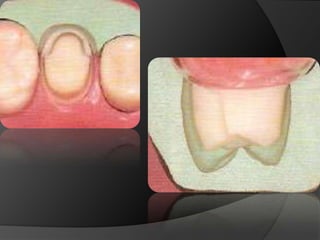

CARILLAS EN CERÁMICA: Alternativa menos agresiva cuando lo que se busca es el cambio de color o de forma en la superficie vestibular

CARILLAS EN CERÁMICA:Alternativa menos agresiva cuando lo que se busca es el cambio de color o de forma en la superficie vestibular